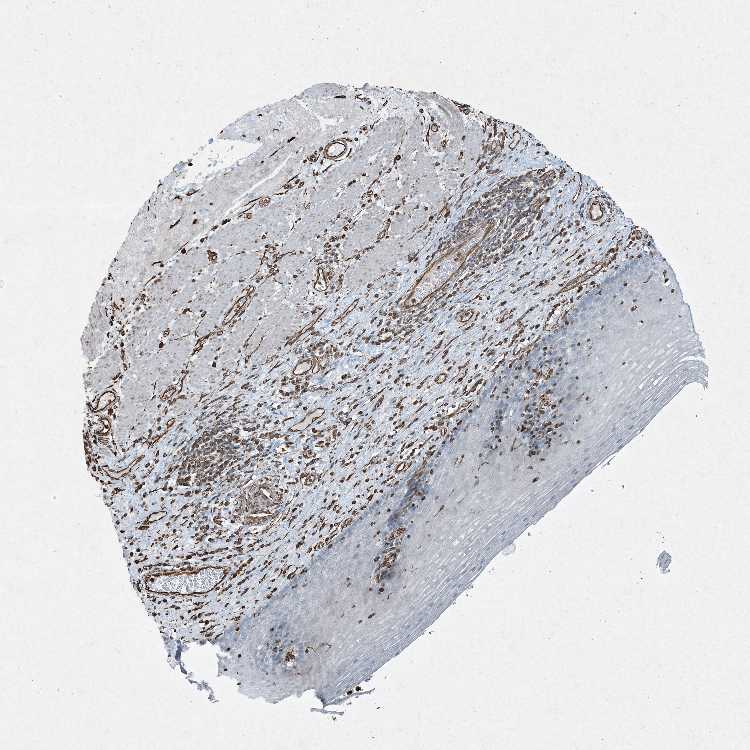

ESOPHAGUS - Antibody stainingi

Antibody staining in the annotated cell types in the current human tissue is reported as not detected, low, medium, or high, based on conventional immunohistochemistry profiling in selected tissues. This score is based on the combination of the staining intensity and fraction of stained cells.

Each image is clickable and will lead to virtual microscopy that enables deeper exploration of all samples and also displays staining intensity scores, fraction scores and subcellular localization as well as patient and tissue information for each sample.

Antibody HPA045503Antibody CAB034117Antibody CAB080389

Squamous epithelial cells MediumNot detectedHigh